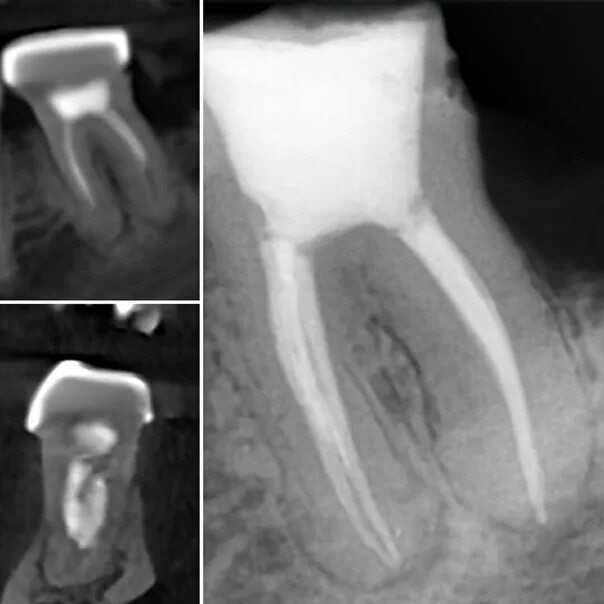

Удалить нервы запломбировать